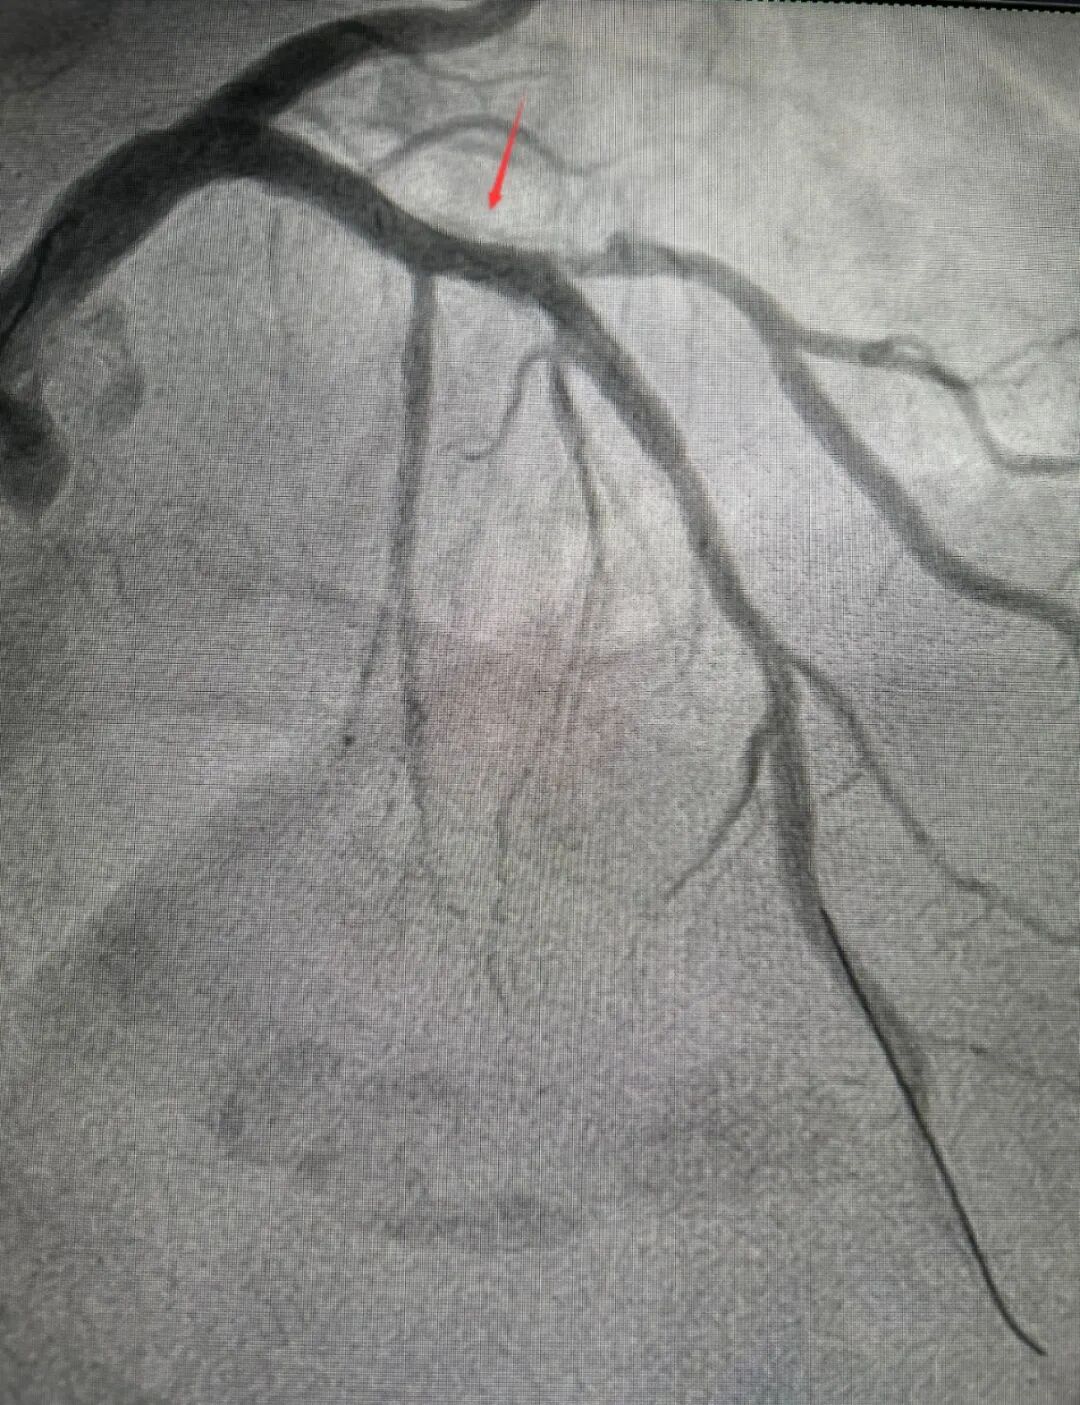

术中,医生发现由于张大妈动脉钙化严重,血管通道狭窄,普通预扩张球囊与超声导管均无法穿越病变。但好在术前做了充足准备,面对这一情况团队立即采用备选方案——冠状动脉旋磨术。手术成功开通被钙化斑块堵塞的血管,术后张大妈症状明显缓解,恢复良好。

是当前心血管疾病治疗领域的“利器”,被称为心血管医生的“金刚钻”。针对严重的钙化病变,该技术采用带有钻石颗粒的旋磨头,依据“差异切割”原理,精准消除血管壁上的“石斑块”,同时减少对血管壁的损伤。对于严重狭窄伴钙化或纤维化的病变,旋磨术通过物理方法有效祛除斑块,提高治疗效果,降低远期再狭窄率。

对于患者而言,该类手术可避免开胸搭桥,减少术中损伤,恢复时间更快。冠状动脉旋磨术的优势体现在其对硬性钙化病变的处理能力、支架植入的辅助作用以及在复杂病变中的灵活应用。这使得它在传统球囊扩张术无法奏效的情况下,成为一种有效的补充治疗手段。